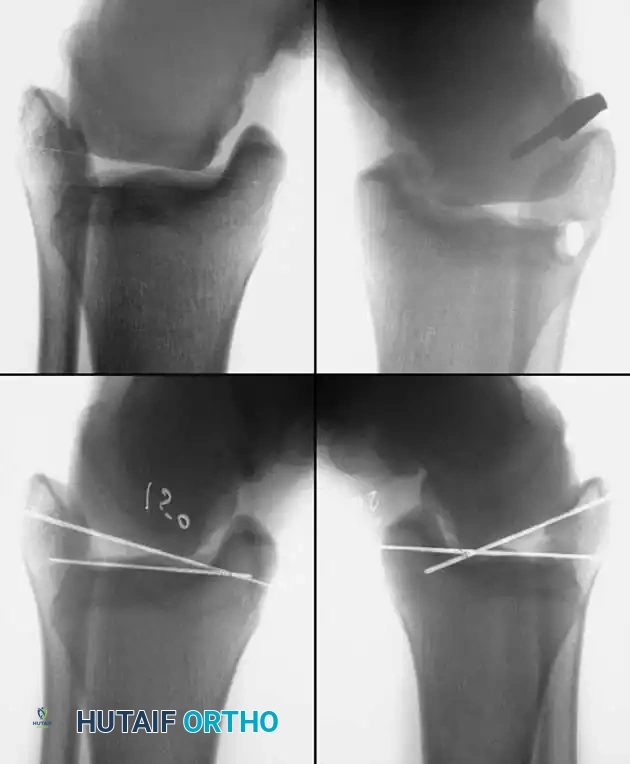

Repair of Acute Rupture of the Lateral Ligaments

The modified Broström-Gould procedure remains the gold standard for anatomic repair of the lateral ligamentous complex.

Surgical Technique:

1. Positioning: The patient is placed supine with a bump under the ipsilateral hip to internally rotate the leg, bringing the lateral malleolus into direct view. A thigh tourniquet is applied.

2. Incision: A 4- to 5-cm curvilinear incision is made along the anterior border of the distal fibula, extending toward the sinus tarsi.

3. Dissection: Care is taken to identify and protect the intermediate dorsal cutaneous branch of the superficial peroneal nerve superiorly and the sural nerve inferiorly.

4. Capsulotomy: The extensor retinaculum is identified and mobilized. A vertical arthrotomy is performed 2 mm anterior to the fibular margin, leaving a small cuff of tissue for repair.

5. Joint Inspection: The joint is inspected for osteochondral lesions or loose bodies.

6. Ligament Repair: The torn ends of the ATFL and CFL are identified. If the tissue is robust, direct end-to-end repair is performed using non-absorbable sutures (e.g., 0 or 2-0 FiberWire). If the ligaments are avulsed from the fibula, suture anchors (typically 2.5 mm to 3.0 mm) are placed into the anterior border of the lateral malleolus.

7. Gould Modification: The inferior extensor retinaculum is mobilized and advanced proximally and laterally over the repaired ligaments, suturing it to the fibular periosteum. This imbrication reinforces the repair, limits inversion, and helps address subtalar instability.

For chronic instability with severely attenuated tissues, non-anatomic tenodesis (e.g., Chrisman-Snook or Watson-Jones) or anatomic reconstruction using allograft/autograft may be required.